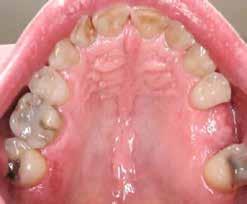

a–d. ábra: Műtét előtti állapot mind a négy páciensnél.

Az alábbi esettanulmányhoz négy pácienst választottunk ki (1. táblázat). Minden esetben egy, vagy több fog pótlására volt szükség, amelyhez kerámiaimplantátumokat használtunk. Valamennyi páciens általános egészségügyi állapota jó volt.

1a 1c 1b 1d Nem Életkor (évek) Egészségügyi állapot Dohányzás Periodontális állapot Foghiány Eset 1 Férfi 52 ASA I Nem Egészséges #35 Eset 2 Férfi 43 ASA I Nem Egészséges #25 & 26 Eset 3 Férfi 57 ASA I Nem Egészséges #16 & 26 Eset 4 Férfi 61 ASA I Nem Egészséges #26 1. táblázat: A páciensek adatai.